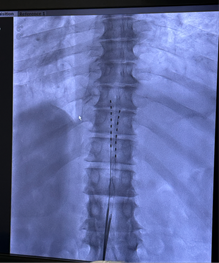

from clipboard

电极植入到位

手术在DSA引导下进行,在肖红教授指导下,由银燕教授、卢帆医生组成的手术团队精准将电极送达患者相应节段的硬膜外腔,并在术中完成刺激参数调试。患者当场反馈,电刺激覆盖范围与疼痛区域高度一致,镇痛效果立竿见影,手术过程顺利完成。